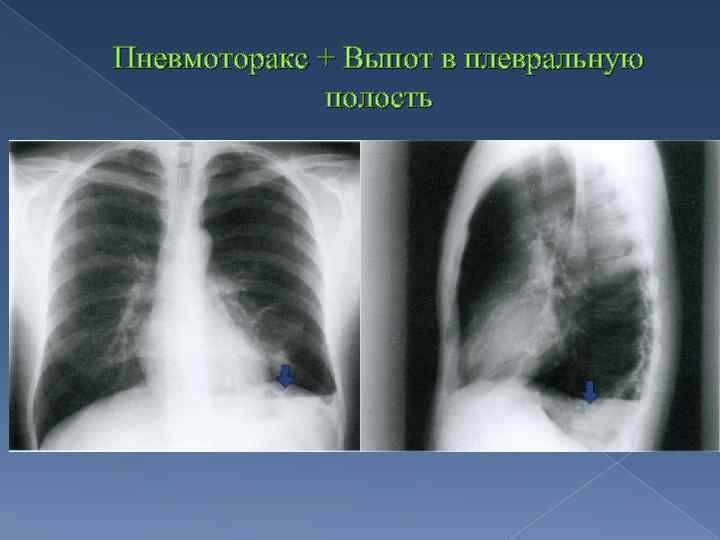

Диагностика плеврального выпота: что нужно знать